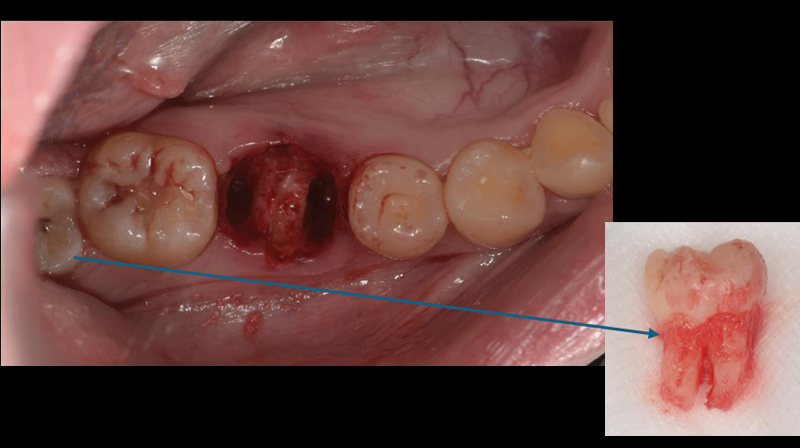

拔除右下第一大臼齒

拔除智齒,固定至第一大臼齒缺牙區域